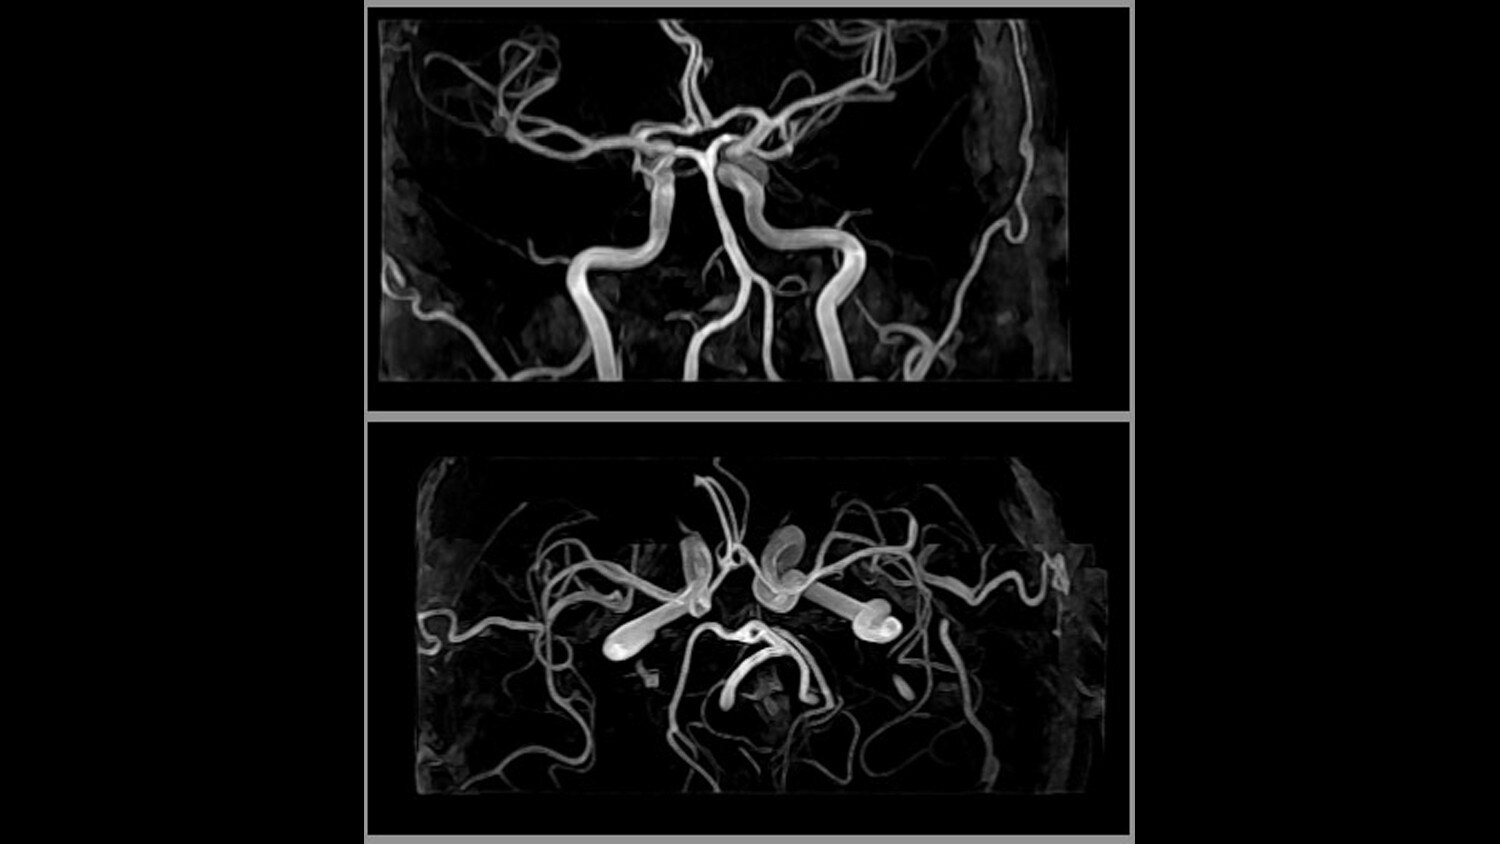

Its full 3.0T magnet and 70 cm bore work together to generate extraordinary image quality without compromises. The result for clinicians is new levels of diagnostic performance.

MultiDrive RF Transmit Fully automated and independent RF pulse amplitude and phase control produce consistently clear 3.0T images.

A large usable field of view is needed to properly image off-center anatomy such as a shoulder or hip. So the Discovery* MR750w features a 70 cm flared, open bore design with a large 50 x 50 x 50 cm field of view.

Intuitive applications help clinicians utilize the full potential of 3.0T MR imaging.